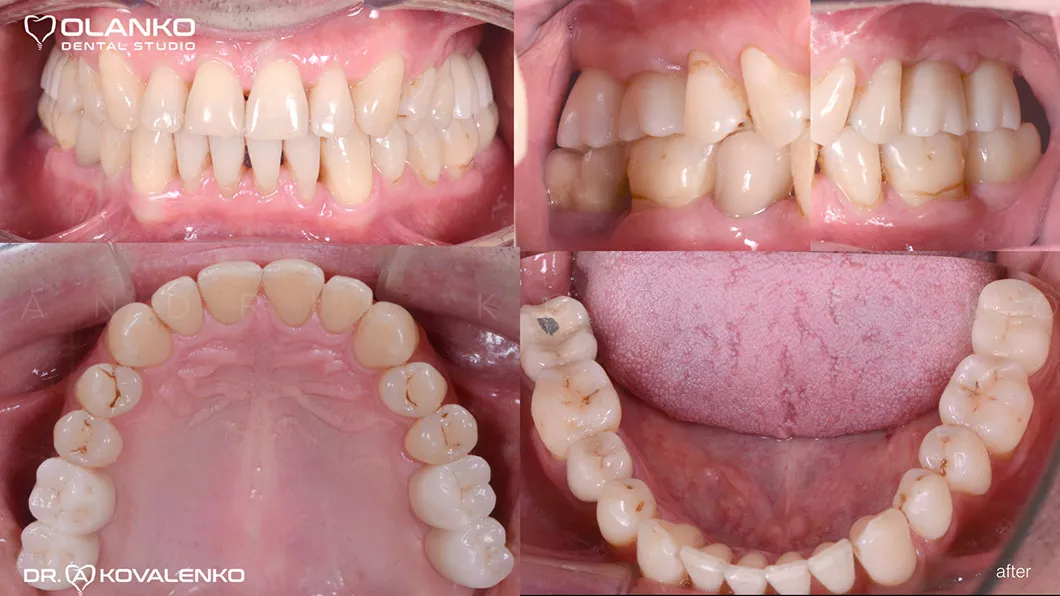

Пациент обратился с жалобами на отсутствие жевательной группы зубов.

Лечение: операция костной пластики на верхней челюсти (двухсторонний синус-лифтинг). Установка 4-х зубных имплантатов на верхней челюсти и один зубной имплантат на нижней челюсти. Пластика мягких тканей в области имплантатов.

Керамические коронки зафиксированы на имплантаты

До и После:

после